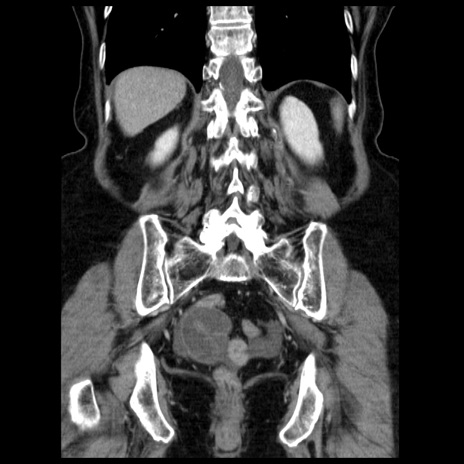

横断像